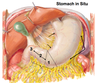

Label parts of stomach: